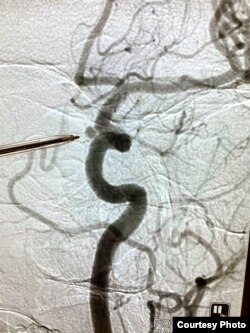

Работа Александры Михайловой из серии "Ломаные пиксели". Врач показывает на снимке место, где была локализована аневризма